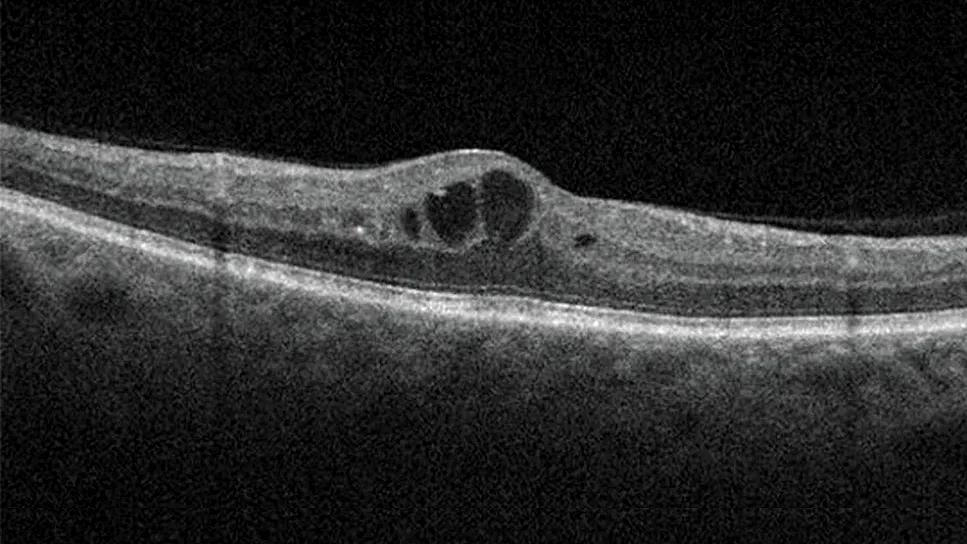

Diabetic macular edema compared to a healthy retina

Optical coherence tomography images demonstrate center-involved DME compared to a retina with no edema.

DME, defined as thickening of the retina, can occur in any stage of diabetic retinopathy and is the most common complication of diabetic retinopathy that causes vision loss.7,8 DME can be divided into center-involved DME, which is thickening in the center of the macula and has greater risk for vision loss, or noncenter-involved DME.8